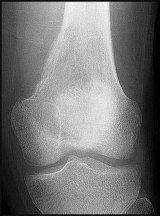

Figures 5a and 5b are the radiographs of a 74-year-old man with poorly differentiated squamous cell carcinoma of the lung. He has had an uneventful recovery after undergoing a wedge resection of his left upper lobe 6 months ago. He is experiencing left lateral knee pain, and a whole-body positron emission tomography/CT scan shows no avid area other than the lateral left distal femur. This patient has needed to use a wheelchair for 3 weeks because of his pain. You discuss these treatment options: aggressive curettage, local adjuvant treatment, cementation, and prophylactic fixation vs distal femoral resection and megaprosthesis total knee arthroplasty reconstruction. You should tell him that

Distal femoral megaprosthetic reconstruction after tumor resection is a reliable oncologic procedure, but 5-year implant survival is as low as 74% with an approximate 8% deep infection rate. The amputation rate is as high as 8% because of infection or recurrence, and there is an overall 18% revision rate. More than 10% of distal femoral megaprosthetic reconstructions are performed to address metastatic disease.

Fixation failure and infection may occur with either procedure. Radiation may not be recommended after a megaprosthesis reconstruction unless margins are not free of tumor. Either operation may be equally successful in returning patients to functional activities. Overall disease-free survival is related to the aggressiveness of the tumor and not the type of reconstruction performed.